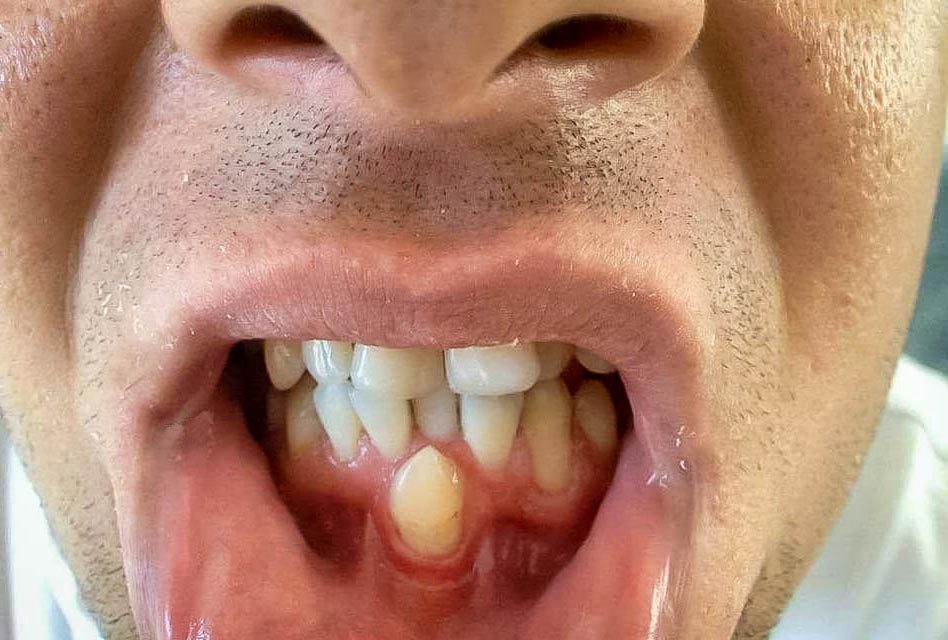

Hyperdontia: the presence of extra (supernumerary) teeth.

Below are examples of mild cases, and examples of extreme cases.

MILD CASES

Hyperdontia is the condition of having supernumerary teeth, or teeth that appear in addition to the regular number of teeth. They can appear in any area of the dental arch and can affect any dental organ.

There is evidence of hereditary factors along with some evidence of environmental factors leading to this condition. While a single excess tooth is relatively common, multiple hyperdontia is rare in people with no other associated diseases or syndromes. Many supernumerary teeth never erupt, but they may delay eruption of nearby teeth or cause other dental or orthodontic problems. Molar-type extra teeth are the rarest form. Dental x-rays are often used to diagnose hyperdontia.